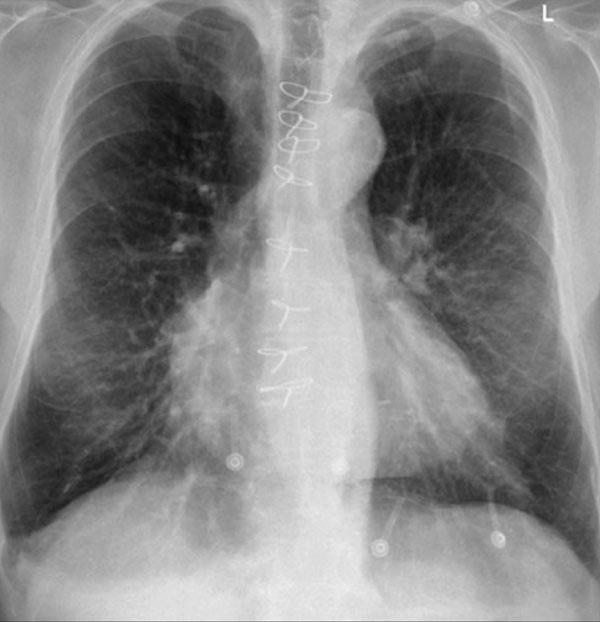

Ví dụ Lâm sàng: Dấu hiệu Kín đáo của Suy tim Sung huyết

Hãy bắt đầu bằng cách xem xét các phim X-quang ngực hiện tại.

Chỉ dựa trên các hình ảnh này, người đọc có thể nghi ngờ suy tim sung huyết (CHF), mặc dù các dấu hiệu còn khá kín đáo.

Bây giờ hãy xem lại phim cũ trước đó…

Việc cuộn qua lại giữa phim hiện tại và phim cũ giúp tăng đáng kể độ tin cậy trong chẩn đoán suy tim sung huyết.

Các dấu hiệu so sánh chính bao gồm:

- Kích thước tim: Tăng nhẹ so với phim trước; tuy nhiên, tim to đã hiện diện từ trước.

- Hệ mạch máu phổi: Cương tụ mạch máu nhẹ gợi ý tăng áp lực tĩnh mạch phổi.

- Hình ảnh mô kẽ: Dấu hiệu kín đáo của phù mô kẽ.

- Tràn dịch màng phổi: Tràn dịch lượng ít hai bên, với thay đổi kín đáo ở bờ dưới-sau của các thùy dưới, gợi ý tích tụ dịch.